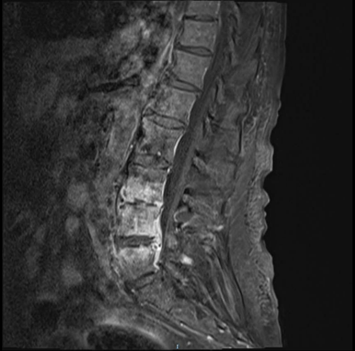

A comprehensive clinical evaluation, including laboratory tests, imaging studies, and blood cultures, was conducted to establish a differential diagnosis for the patient's lumbar pain and systemic symptoms. Laboratory work revealed elevated C-reactive protein (CRP) levels (100 mg/L), hypercalcemia (15.3 mg/dL), and positive blood cultures for *S. epidermidis*. Imaging studies included a transthoracic echocardiogram (TTE) showing a previously documented mitral valve prolapse and a PET-CT scan that revealed high uptake in the lumbar vertebrae (L3, L4, L5). Subsequent lumbar MRI with contrast confirmed the presence of phlegmonous inflammatory changes suggestive of spondylodiscitis (Figure 1 & 2).

Figure 2 MRI with contrast: Phlegmonous inflammatory changes in L3-L4 and L4-L5 suggestive of spondylodiscitis.